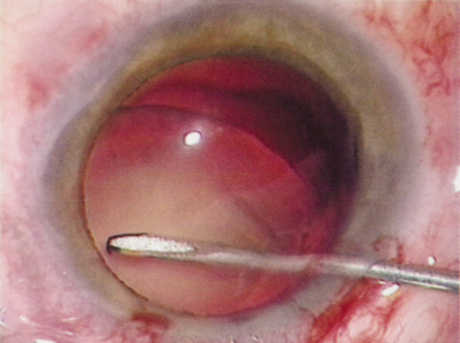

ANTERIOR CAPSULOTOMY

One of the most beneficial techniques developed over the last decade is capsulorrhexis. A continuous curvilinear anterior capsular opening helps prevent intraoperative and postoperative complications. With capsulorrhexis, mechanical strength of the capsular opening is superior to that in a can-opener capsulotomy; thus, a tear to the posterior capsule with subsequent vitreous loss is much less likely.96 Capsulorrhexis allows for nuclear manipulation with less risk of posterior capsule rupture. Cortex removal is made easier as well, because it becomes easier to differentiate cortical material from anterior capsule. Should a posterior capsular tear occur, sulcus fixation is more likely attainable with the presence of a clearly visible residual anterior capsular rim. Placement of both IOL haptics into the capsular bag is more certain with capsulorrhexis because the surgeon can more easily visualize the haptics gliding beneath the anterior capsular rim.

Capsulorrhexis can be performed with a cystitome, capsulorrhexis forceps, or combination-type instruments. Regardless of which instrument is used, several principles can help the surgeon successfully complete capsulorrhexis. It is important to maintain the anterior chamber, because making the chamber shallow increases tension on the zonules and causes the tear to run peripherally. The authors recommend the use of a viscoelastic agent for maintaining chamber depth and, of course, for endothelial protection. Therefore, if the tear begins to run peripherally, the surgeon should redeepen the anterior chamber before attempting to redirect the tear. Additionally, folding the capsule margin can aid the surgeon in redirecting the tear more accurately (Fig. 10).

Fig. 10. The capsulorrhexis tear is more easily redirected by folding the capsule over, in advance of the tear.